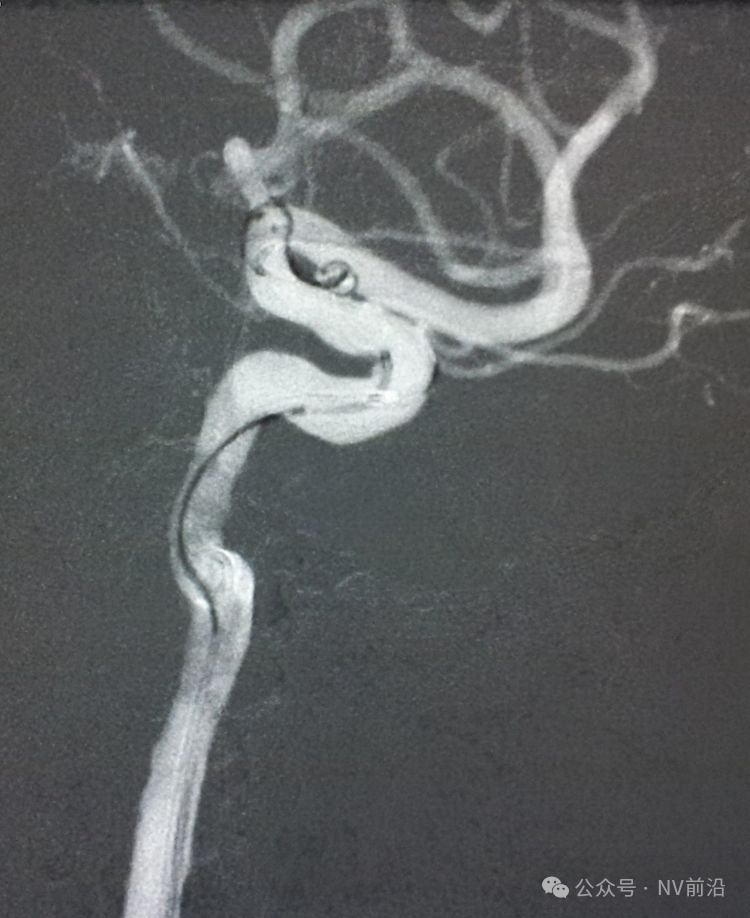

工作位造影

Traxcess 14微导丝可以进入瘤腔,但头端塑成S形的Echelon 10微导管无法跟入。

将微导管在虹吸弯处成襻,越过瘤颈,管头折返钩入瘤腔,即所谓回马枪技术。